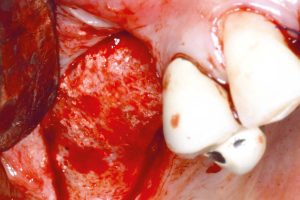

Osteokonduktivita maxresorb® je založena na matici vzájemně propojených pórů, velmi vysoké celkové pórovitosti cca. 80% stejně jako jeho hrubý nanostrukturovaný povrch, který usnadňuje adsorpci krve, proteinů a kmenových buněk a podporuje buněčnou diferenciaci a kostní integraci. maxresorb® je tedy ideálním skeletem pro migraci buněk tvořících kosti a vazbu signálních molekul, což urychluje integraci a regeneraci tkání.

IMPLANTOLOGIE, PARODONTOLOGIE A ÚSTNÍ A CMF CHIRURGIE

- Sinus lift

- augmentace alveolu

- Intraoseální vady

- Augmentace extrakční rány

- Kostní defekty

- Furkační defekty